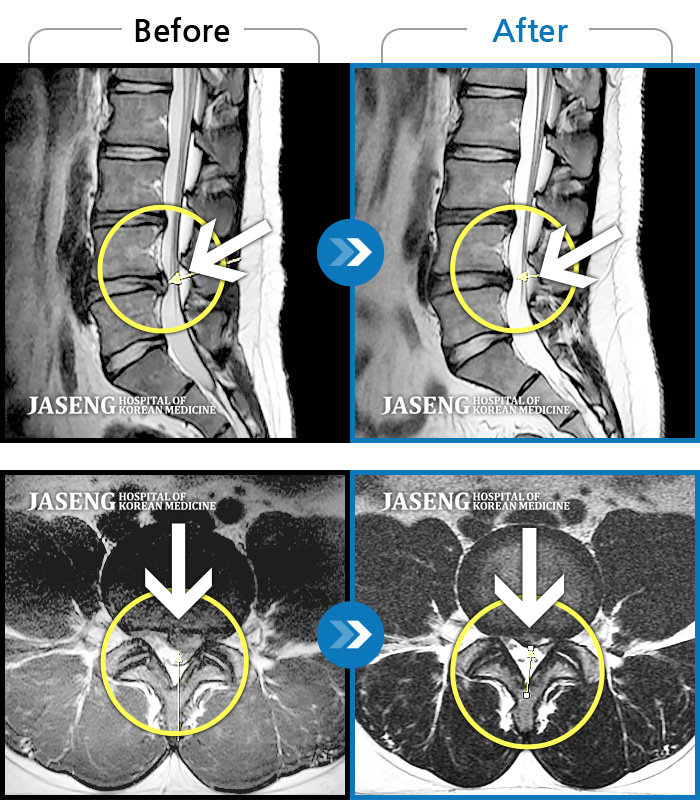

허리디스크

울산 · 정운석 원장

하요추부 통증과 양측 대퇴부 후면 저림

촬영시기

2020.01.10 ~ 2022.08.20

2022.08.26